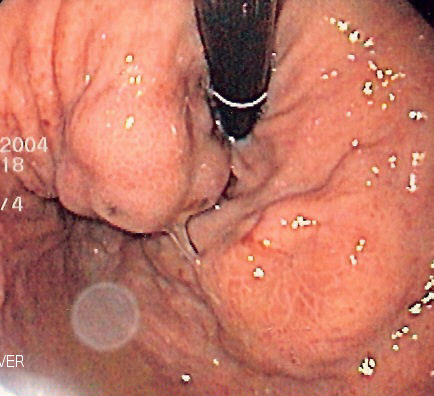

📍دوالي المريء عبارة عن أوردة غير طبيعية متضخمة

📍في الوضع الطبيعي اوردة المريء لا تظهر ولكن عند حدوث التليف يرتفع ضغط الدم في الوريد البابي وبالتالي يؤدي الى امتلاء أوردة المريء بالدم وبالتالي تظهر هذه الاوردة وتسمى بدوالي المريء ويتم اكتشافها بالمنظار او الاشعة المقطعية

🔆 أنواع دوالي المريء والمعدة

✅ لذلك يحرص الطبيب على اتخاذ كافة الاجراءات الوقائية لتجنب النزيف عند اكتشاف الدوالي عن طريق الفحص المبكر حيث ينصح كل مرضى تليف الكبد بعمل منظار الجهاز الهضمي العلوي عند التشخيص